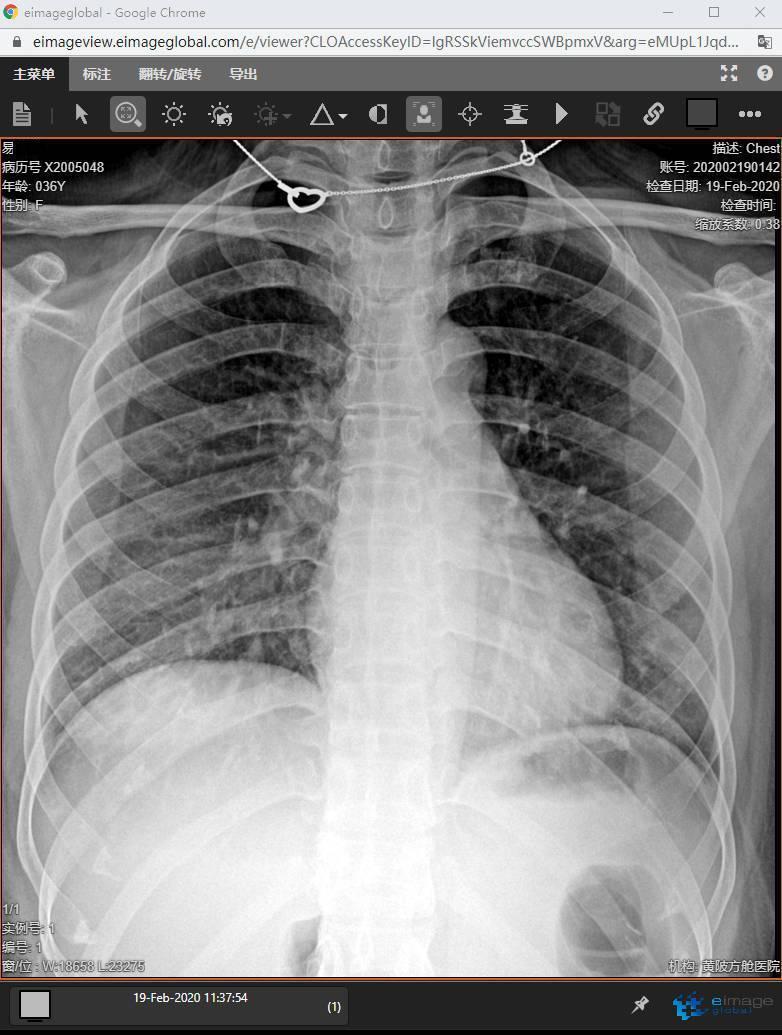

2月19日,在武漢黃陂區(qū)的“黃陂方艙醫(yī)院”簡陋的DR工作室里,浙江省人民醫(yī)院醫(yī)療隊俞亮技師剛剛給36歲的“新冠肺炎”患者易女士拍完胸片,她的影像被迅速地通過網(wǎng)絡(luò)傳輸?shù)皆贫朔?wù)器。千里之外的“黃陂方艙醫(yī)院”后方大本營、浙江省人民醫(yī)院放射科龔向陽主任等專家組立刻借助遠程影像系統(tǒng),對易女士的胸片進行認真解讀,并將診斷意見發(fā)送給身在武漢的緊急醫(yī)學救援隊員隊員、放射科管政醫(yī)生。

位于武漢市黃陂區(qū)的“黃陂方艙醫(yī)院”,是由浙江省人民醫(yī)院國家緊急醫(yī)學救援隊全面接管的一家“方艙醫(yī)院”。雖然以接收輕癥患者為主,但是需要及時發(fā)現(xiàn)病情變化,及時將重癥患者轉(zhuǎn)往有救治能力的醫(yī)院。胸部影像檢查是評估病情變化的有效手段,在臨時改建的方艙醫(yī)院里,胸部影像學檢查意義重大,它能為臨床醫(yī)生提供更清晰的診療依據(jù)。